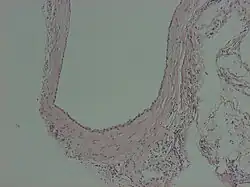

A peritoneal inclusion cyst is a cyst-like structure that appears in the pelvis due to non neoplastic reactive mesothelial proliferation, often as a consequence of prior episodes of pelvic inflammation, as can occur in pelvic inflammatory disease. It has the potential to mimic ovarian cysts, hydrosalpinx or even malignancy, due to its nonspecific anechoic appearance.[1]

Peritoneal inclusion cysts are commonly visualized on ultrasonography as a spider-web-like pattern. A normal-looking ovary is encircled by a big, irregular or oval, echolucent cyst with fine internal septations. The ovary is frequently located in the middle of the inclusion cyst or on its lateral aspect, appearing to be dangling inside the cyst.[2] Peritoneal inclusion cysts appear as a cystic mass with regular or irregular boundaries on CT scans, including material that has fluid or hemorrhagic attenuation properties. Cystic lesions with low T1 signal and high T2 signal, consistent with serous fluid, are shown on MR imaging.[7]